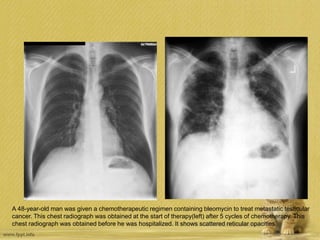

A 48-year-old man was given a chemotherapeutic regimen containing bleomycin to treat metastatic testicular

cancer. This chest radiograph was obtained at the start of therapy(left) after 5 cycles of chemotherapy. This

chest radiograph was obtained before he was hospitalized. It shows scattered reticular opacities.